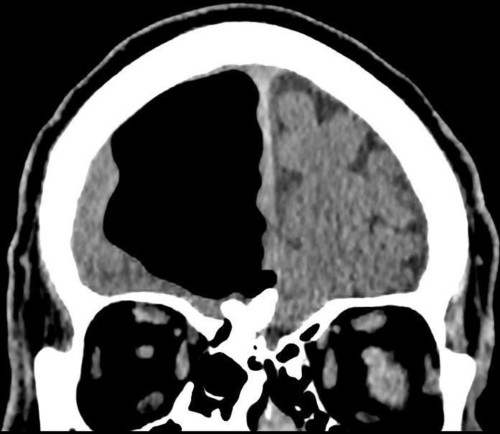

Срезы КТ печатаются в негативе на плёнке, точно так же, как в начале двадцатого века (в 1895 делали на пластинах, а не плёнке). Но съёмка идёт на матрицу, примерно как в профессиональной зеркалке, только улавливающей рентген-излучение. Поскольку в медицинских вузах никто не обновлял стандарты, врачи умеют работать с инвертированным изображением и на плёнке, и томографы отдают им картинку именно в том виде, в котором её можно отнести на просмотровый стол и просветить. Переворачивать изображение в истинные цвета (делать из негатива позитив) не принято по той же причине. Просмотровые столы в нашей клинике не используются, но стоят в каждом кабинете, потому что таков норматив.

В целом, врачу никогда не придёт в голову учить пациента читать КТ, потому что это бессмысленно. Но я подумал: а почему бы и нет? Конечно, вы не наработаете 20-летний опыт определения разных сложных случаев по рентгеновской тени тканей, но, по крайней мере, сможете определить 40–50% базовых картин.

Я покажу, как выглядит воспалённая пазуха, металл, запломбированные и незапломбированные каналы, очаги.